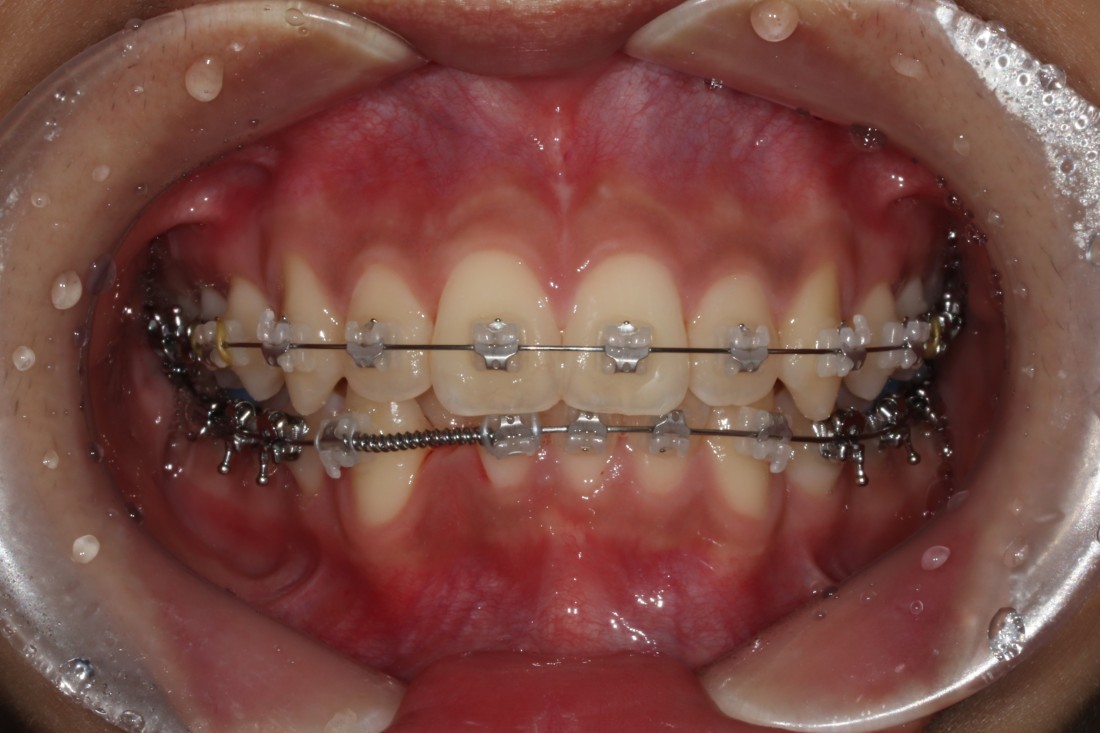

다양한 과개교합 교정 전/후 사진은

위의 사진을 클릭하시면 확인하실 수 있으며,

윗니에 아랫니가 거의 덮여있는

과개교합의 경우에는

턱관절 장애를 유발합니다.

윗니가 아랫니를 거의 덮어서

보이지 않을 정도의 부정교합의 종류인데요.